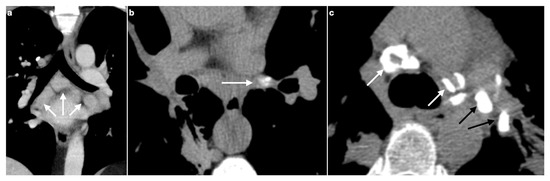

CT Imaging Features of Pulmonary Sarcoidosis: Typical and Atypical Radiological Features and Their Differential Diagnosis

by Elisa Baratella, Valeria di Luca, Alessandra Oliva, Ilaria Fiorese, Antonio Segalotti, Marina Troian, Stefano Lovadina, Barbara Ruaro, Francesco Salton, Roberta Polverosi and Maria Assunta Cova

Sarcoidosis is a chronic, idiopathic, multisystemic inflammatory disease characterized by non-caseating granulomas, most commonly affecting the lungs and mediastinal lymph nodes. Radiological imaging plays a fundamental role in the diagnosis, assessment of disease extent, and differentiation from other pulmonary conditions. This narrative review offers a comprehensive overview of the imaging features of pulmonary sarcoidosis, focusing on both typical patterns—such as bilateral hilar lymphadenopathy, perilymphatic nodules, and upper lobe-predominant infiltrates—and atypical manifestations—including alveolar opacities, miliary nodules, fibrocystic changes, and lower lobe involvement. Emphasis is placed on the utility of high-resolution computed tomography (HRCT) in detecting early parenchymal changes and complications such as fibrosis, bronchiectasis, and pulmonary hypertension. Differential diagnosis, including tuberculosis, silicosis, metastatic disease, organizing pneumonia, and hypersensitivity pneumonitis, are discussed to aid interpretation. Recognizing the spectrum of radiological presentations is essential for distinguishing sarcoidosis from other interstitial and granulomatous lung diseases. Radiologists play a pivotal role in the multidisciplinary diagnostic process, contributing to timely diagnosis, risk stratification, and optimized patient management. Full article